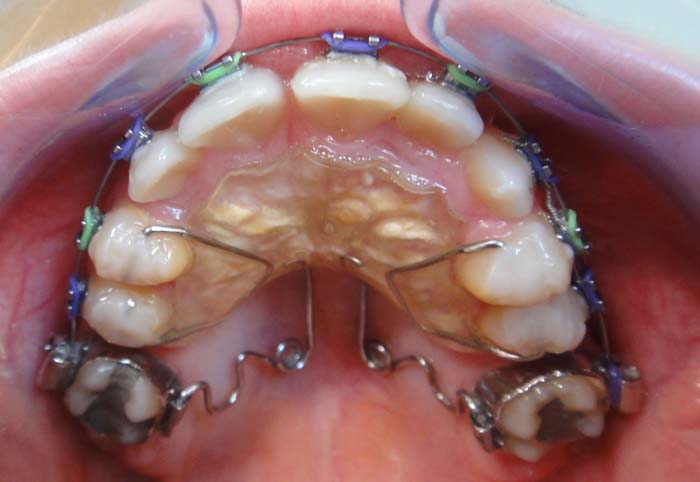

Aparat se sastoji od ortodontskih prstenova koji se cementiraju na prve stalne molare, okluzalnih žičanih naslona koji su postavljaju u jamice na griznim površinama premolara i pričvrste za zub pomoću kompozitnih materijala. Zatim, od akrilatnog tela koje prekriva krov usta (nepce) i opruga koje se pričvršćuju za prstenove. Opruge prave pritisak i pomeraju molare unazad.

Pendulum aparat se koristi za pomeranje gornjih molara unazad. Time se stvara prostor za ostale stalne zube da bi mogli da niknu u dobrom položaju, dok se istovremeno koriguje i zagrižaj.